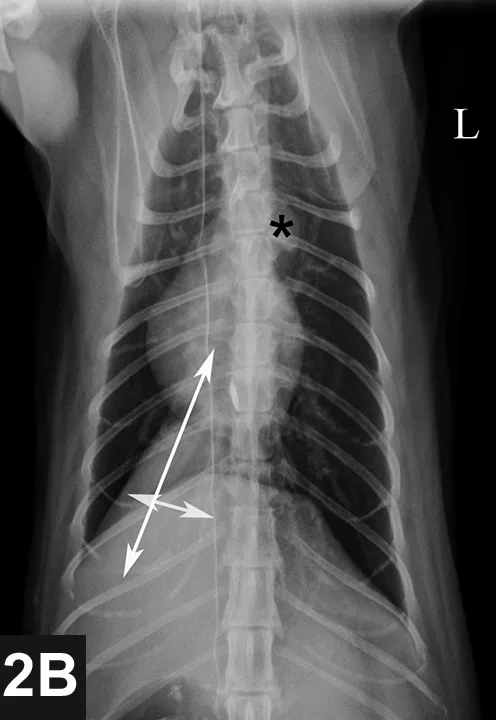

Thoracic radiographs (Figures 2A and 2B) were obtained to check for primary or metastatic neoplasia; an approximately 8.3 cm long, 3.8 cm tall, and 3.6 cm wide soft-tissue mass was present in the dorsal aspect of the right caudal thorax (white arrows), occupying the majority of the right caudal lung lobe. The aortic arch is prominent in the ventrodorsal view (black *); this is common in geriatric felines and may be a variation of normal or possibly an indication of systemic hypertension. The finding of a mass in the lung of this cat supports a diagnosis of a primary pulmonary carcinoma originating from the right caudal lung lobe with metastasis to the third digit of the right pelvic limb. This syndrome is described in several case reports.1-3 Most cats have swelling of one or more digits with radiographic evidence of osteolysis of the affected digit(s). The tendency of feline pulmonary carcinomas to metastasize to one or more digits is not understood, and no specific treatment has been rewarding.

VD thoracic x-ray of cat with symbols marking aortic arch and soft-tissue opacity mass in the caudal right field.

FIGURE 2B